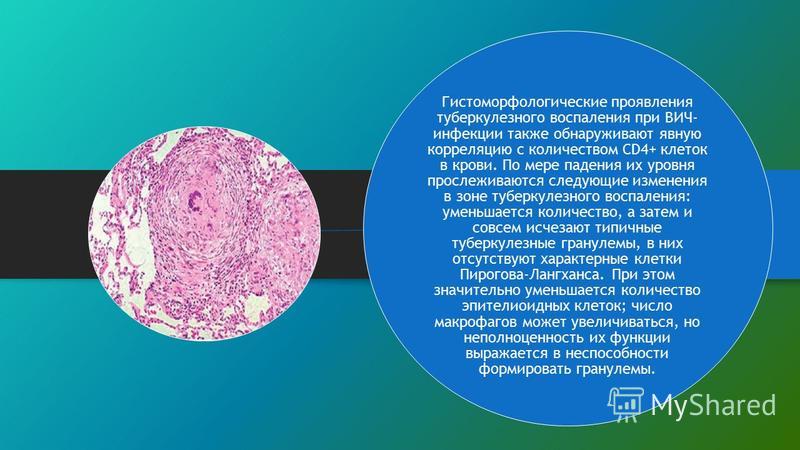

Микроскопический взгляд на мишитарный туберкулез легкого: фотодокументация

Раздел: Снимки-откровения